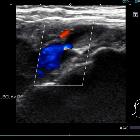

Subclavian

vein aneurysm - Case presentation and discussion. Gray scale and Color Doppler exploration demonstrates the aneurysm and an echogenic image attached to a wall in its interior, compatible with mural thrombus.

vein aneurysm - Case presentation and discussion. Gray scale and Color Doppler exploration, orthogonal to Fig. 3a, demonstrates the aneurysm and an echogenic image attached to a wall in its interior, compatible with mural thrombus.